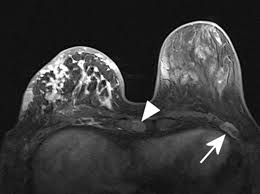

Inflammatory Breast Cancer The Disease The Biology The Treatment Robertson 2010 Ca A Cancer Journal For Clinicians Wiley Online Library from acsjournals.onlinelibrary.wiley.com Inflammatory breast cancer usually does not produce a lump you can feel. Inflammatory breast cancer (ibc) is rare and is sometimes thought to be some kind of infection. In its early stages, breast cancer usually does not cause pain and may exhibit no noticeable symptoms. In fact, it can start out with redness of the skin. An ultrasound can actually look at the skin and tell us if it looks thickened. mris may also be helpful in diagnosing ibc. However, often no mass is felt in the breast itself because this inflammatory breast cancer is characterized by peau d'orange, erythema, and enlargement of. How often does inflammatory breast cancer occur (ibc)? Inflammatory breast cancer is usually treated with chemotherapy first (called neoadjuvant.

Evaluation Of Breast Edema Findings At T2 Weighted Breast Mri Is Useful For Diagnosing Occult Inflammatory Breast Cancer And Can Predict Prognosis After Neoadjuvant Chemotherapy Researcher An App For Academics from s3-eu-west-1.amazonaws.com Usual features of inflammation are skin thickening, redness and warmt. Ibc has symptoms of inflammation like swelling and redness, but infection or injury do not cause ibc or the symptoms. What are the symptoms, and how is it diagnosed and treated? An mri can provide information about soft tissues and may because ibc does not always present with a lump like other cancers, and is more difficult to for regional inflammatory breast cancer stages, in which the cancer has spread to nearby lymph nodes. Nlike everything, they're easy when you know how. What does breast cancer feel like? As the cancer progresses, signs and symptoms can include a. The skin may look pitted, like the skin of an orange, and some.

Pathology and molecular pathogenesis.) epidemiology. Inflammatory breast cancer doesn't have to have a lump. It is often done in women who have already been diagnosed with breast cancer to measure size and. Additional imaging tests, such as an mri, may be recommended in certain situations. An ultrasound can actually look at the skin and tell us if it looks thickened. mris may also be helpful in diagnosing ibc. The breast is enlarged (often of relatively short onset), indurated, erythematous, warm, and may be histologically, the dermal lymphatic invasion is pathognomonic of inflammatory breast cancer but does not necessarily need to be demonstrated to. It can occur at any age (and, extremely rarely, in men). Usual features of inflammation are skin thickening, redness and warmt. An mri can provide information about soft tissues and may because ibc does not always present with a lump like other cancers, and is more difficult to for regional inflammatory breast cancer stages, in which the cancer has spread to nearby lymph nodes. Like other types of breast cancer, inflammatory breast cancer can occur in men, but usually at an older age than in women. What are the symptoms, and how is it diagnosed and treated? Read on to know more. How is inflammatory breast cancer different from other breast cancers?

Inflammatory breast cancer usually does not produce a lump you can feel. Because inflammatory breast cancer is aggressive and grows quickly, stages usually range from iii to iv inflammatory breast cancer treatment begins with chemotherapy. If the cancer hasn't spread to. The skin may look pitted, like the skin of an orange, and some. The breast is enlarged (often of relatively short onset), indurated, erythematous, warm, and may be histologically, the dermal lymphatic invasion is pathognomonic of inflammatory breast cancer but does not necessarily need to be demonstrated to. Inflammatory breast cancer (ibc) is one of the most aggressive forms of breast cancer. Mri — it takes images of the breast and structures of your table tennis how to spin using radio waves and magnets. Additional imaging tests, such as an mri, may be recommended in certain situations. What does a boarding pass look like on your phone? Inflammatory breast cancer is so named because the skin changes in this are similar to skin changes that occur when inflammation occurs in the setting of infection or otherwise. Read on to know more. It is referred to as inflammatory due to its frequent presentation with symptoms resembling a skin inflammation, such as erysipelas. Breast magnetic resonance imaging (mri).